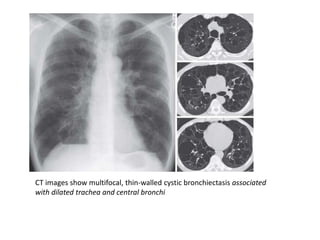

CT images show multifocal, thin-walled cystic bronchiectasis associated

with dilated trachea and central bronchi

Congenital tracheobronchomegaly (Mounier-Kuhnsyndrome) with bronchiectasis. This 73-year-old woman has had recurring respiratory infections throughout her adult life • B-The dilated trachea with prominent cartilaginous rings is confirmed on a CT scan (between arrows). • C, Not only is the trachea Enlarged, but the main-stem bronchi are dilated (between arrows).

CT images showmultifocal, thin-walled cystic bronchiectasis associated with dilated trachea and central bronchi